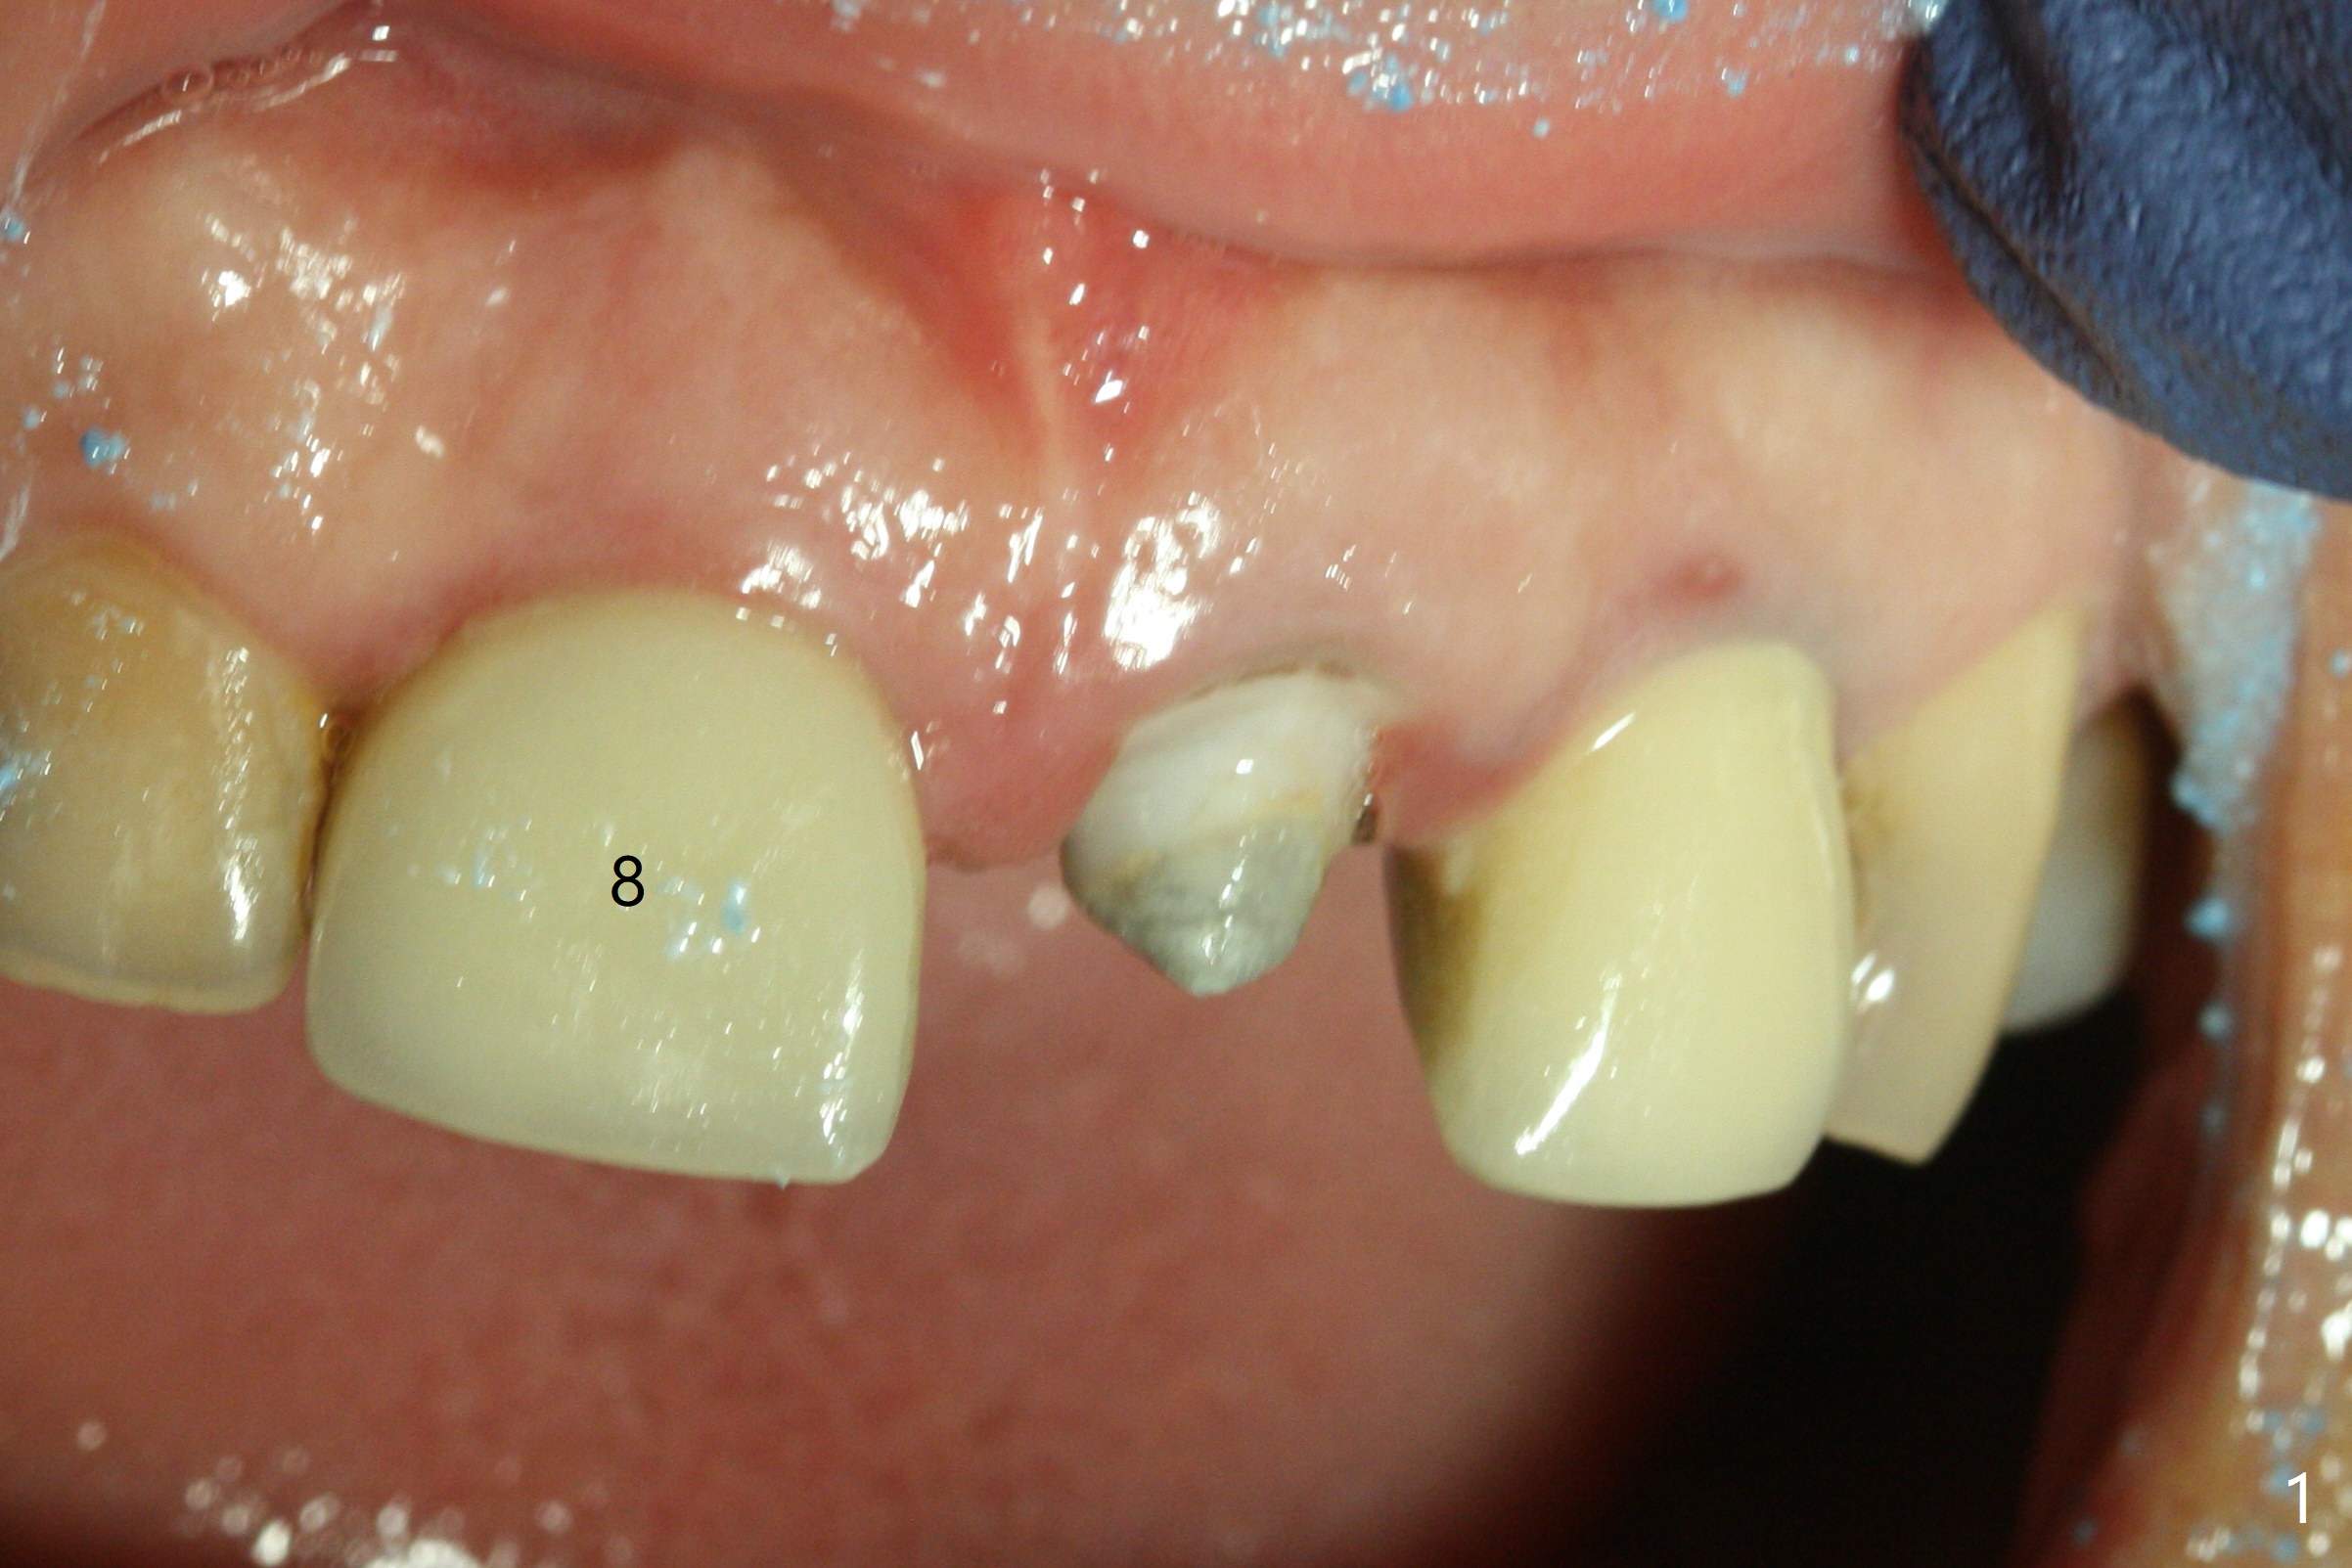

When the 44-year-old woman returns, the crown dislodges from #9 with palatal porcelain chip (Fig.1). Although the post is in place as compared to its dislodgement last visit, it is short and pointed (Fig.2,3 P). Because of the anterior deep bite (Fig.4), an implant restoration may not provide advantage; a new build-up is fabricated (B-U) for a new crown (Fig.5-6). The existing crown is reinserted for shade comparison (Fig.7 C). The gingiva at #8 and 9 is healthy, whereas that at #10 is not (Fig.8). PA taken 5 months later shows that the crown at #10 looks normal (Fig.9).